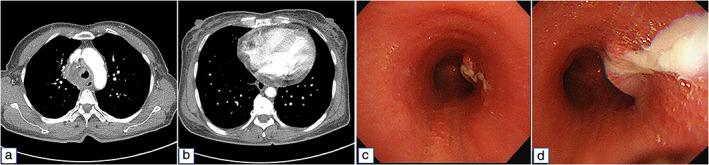

Delayed onset of mediastinitis with tracheomediastinal fistula following endobronchial ultrasound-guided transbronchial needle aspiration; A case report.

Infectious complications after endobronchial ultrasound-guided transbronchial needle aspiration (EBUS-TBNA) are rare but serious. Here, we report a very rare case of delayed onset of mediastinitis with tracheomediastinal fistula after EBUS-TBNA. Surgical debridement was performed, antibiotics were administered, and the postoperative course of the patient was good. Careful monitoring is needed to prevent the possible development of infectious complications after EBUS-TBNA.